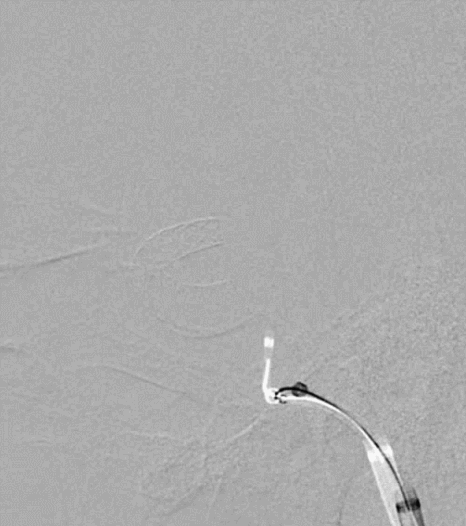

4mm×30mm Streamline

术后4月余随访:多发动脉瘤均未见显影,远端残余轻度狭窄